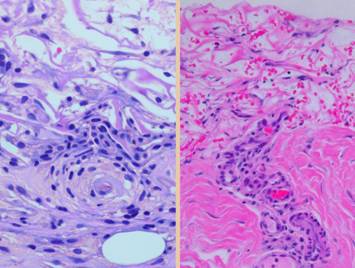

Left, a microscope image of normal wound healing.  The structure shown here is the prototypical wound.  Details of the structure and process will be explained in following panels.  Right, the microscopic appearance of fully regenerated Integra-CG matrix, the details likewise to be explained in following panels.  Even without explaining or focusing on specific details, the dissimilarity of the two can be appreciated.  Angiocytes and fibroblasts, vessels and connectives – that is all there is to these two tissues.  However, by supplying different “rules” or “subroutines” for the interaction and assembly of these elements, two different biomaterials emerge.  The rules or routines are based on the circumstances, reaction-to-injury versus embryonic regeneration.  The results have very different physical properties and implications for daily life, functional adaptations, and potential need for ongoing medical care.

Pictured is matrix regeneration within a piece of Integra collagen-gag matrix.  It is no longer the non-living empty matrix placed on the original wound, but a fully restored living material.  The details of this process are now presented.  However, even without knowing the specific details, it can be appreciated that the structure, morphology, and patterns of this regenerated biological material are different than the microscopic structure of the normal post-inflammatory wound.  Normal wound healing is triggered by inflammation and then evolves according to its own “program” of how angiocytes and fibroblasts rebuild a stroma of blood vessels and connective mesh.  Integra suppresses inflammation, and thus the normal “wound healing program” is never turned on.  Integra “heals” by a fundamentally different mechanism analogous to embryonic tissue generation.  Its build to a state of complete regeneration is uniform throughout the matrix, distributed rather than stratified, and when complete, it has created a new material that has characteristics mostly like normal dermis and quite unlike scar.  The matrix coaxes the same two cells, angiocytes and fibroblasts, to make a new tissue of blood vessels and connective mesh in a patterned morphology that is profoundly different then scar.  The same cells, making the same elemental components, assemble them in a completely different pattern than wound healing and scar because the embryogenesis-and-stromal-generation “program” is entirely different than the healing-and-scar “program”.

37

This is a close up view of a syncytial cluster at its peak before revascularization allows second set histogenesis (discussed on a pending panel, “second set” is the progressive process which includes consolidation of the matrix pores with connective proteins and evolution of the cells to mature fibroblast morphology).  Seen in this cluster are about half a dozen syncytial cells.  They are surrounded by a comparable number of cells that have small lymphoid nuclei.  Identity of these smaller cells is uncertain, either pioneer cells not yet transformed or else secondary or maturing fibroblast forms.  However, the large cells are the focus of this view.  They have enlarged nuclei and cytoplasm.  Cytoplasm is reticulated.  The cells seem confluent in many areas, boundaries being indistinct or intertwined.  Pale pink material adjacent or between these cells is young collagen.  There are no angioid cells, vessels, or erythrocytes.  These cells are at the limit of what they can accomplish without a direct blood supply.  Once a blood supply arrives, they will begin the second set production of fibroblasts and connectives, and Integra pore that hey occupy, their local domain, will begin to consolidate with collagen and a fibrous structure.